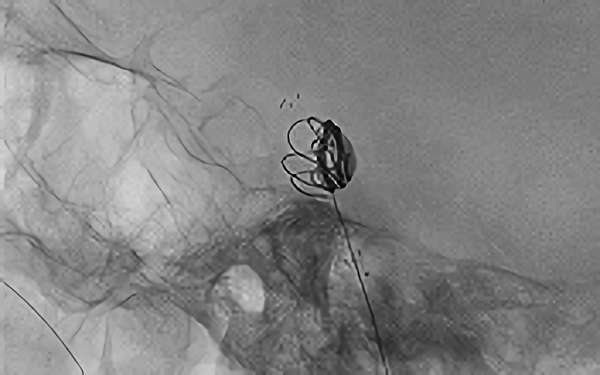

No.1631 手術中